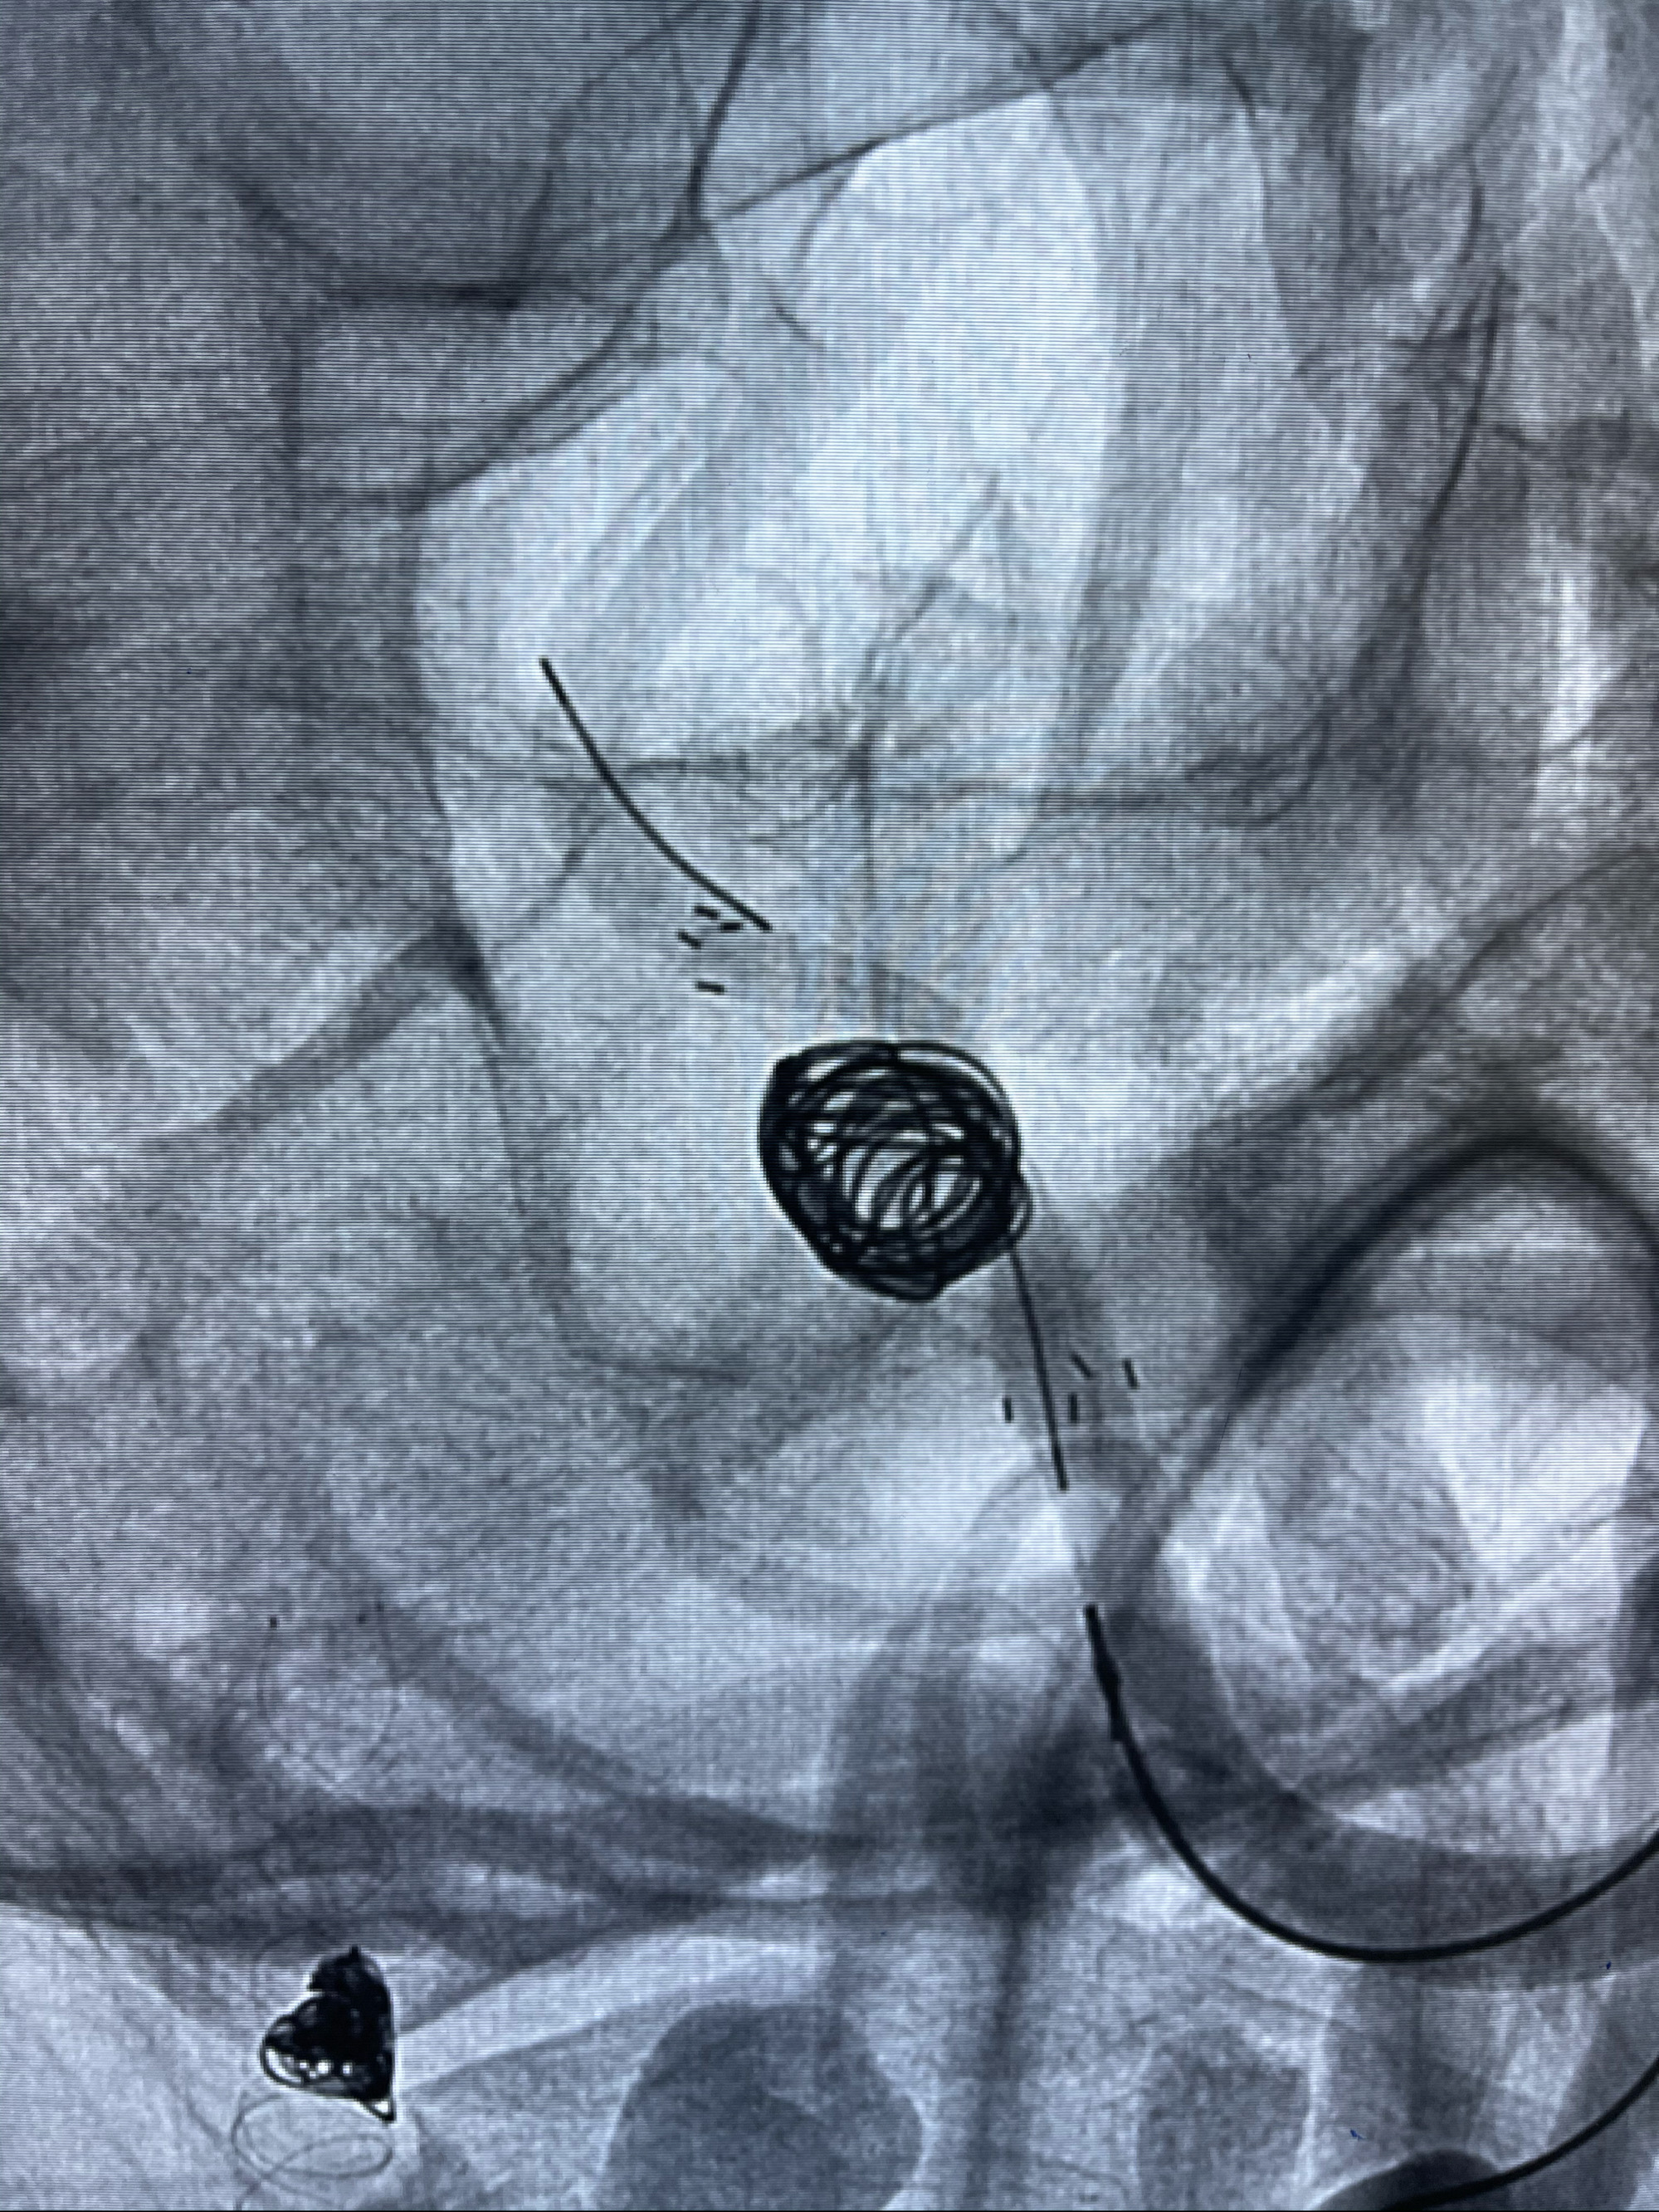

支架到位

支架释放,透视下